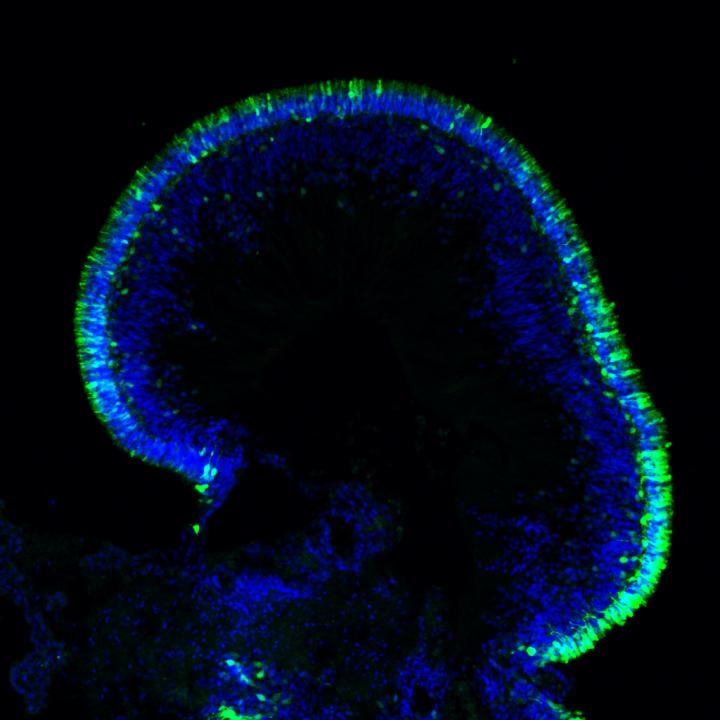

Scientists at the National Eye Institute (NEI) have developed a promising gene therapy strategy for a rare disease that causes severe vision loss in childhood. A form of Leber congenital amaurosis, the disease is caused by autosomal-dominant mutations in the CRX gene, which are challenging to treat with gene therapy. The scientists tested their approach using lab-made retinal tissues built from patient cells, called retinal organoids. This approach, which involved adding copies of the normal gene under its native control mechanism, partially restored CRX function. The study report appears today in Stem Cell Reports . NEI is part of the National Institutes of Health.

To explore how gene augmentation - adding copies of the normal gene - would affect autosomal-dominant LCA, Swaroop's team, developed retinal organoids from two volunteers with LCA and from their unaffected family members. Led by Kamil Kruczek, Ph.D., a postdoctoral fellow in Swaroop's lab, they built the complex retina-like tissues in several stages, starting with skin cells, inducing the production of mature photoreceptors and other retinal cells with the genetic profile of each volunteer. As expected, patient organoids made far less light-sensing opsin than the organoids made from unaffected family members.

The team's gene augmentation strategy restored some CRX protein function for organoids from both patients, driving expression of opsins in both types of photoreceptors: rods and cones.